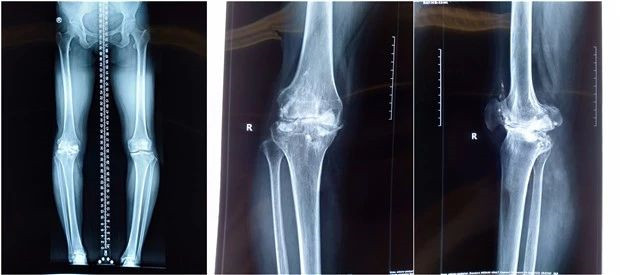

膝关节LCCK术前